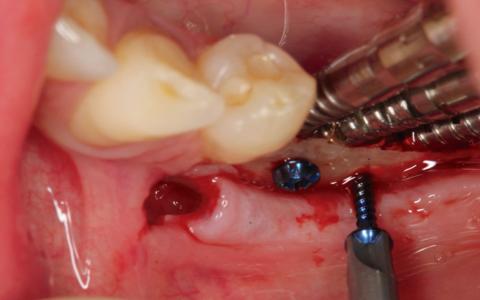

Paciente de 45 años a la que le extrajeron los dientes 45 ,46 y 47 hace unos 17 años. Paciente fumadora sin alteraciones sistemicas, con biotipo fino y una cresta mandibular de 2 mm a nivel transversal.

Plan de tratamiento: Técnica de expansión y colocación de implantes en dos tiempos. Expansión ósea y colocación de tornillos de osteosintesis como parte de la regeneración ósea.